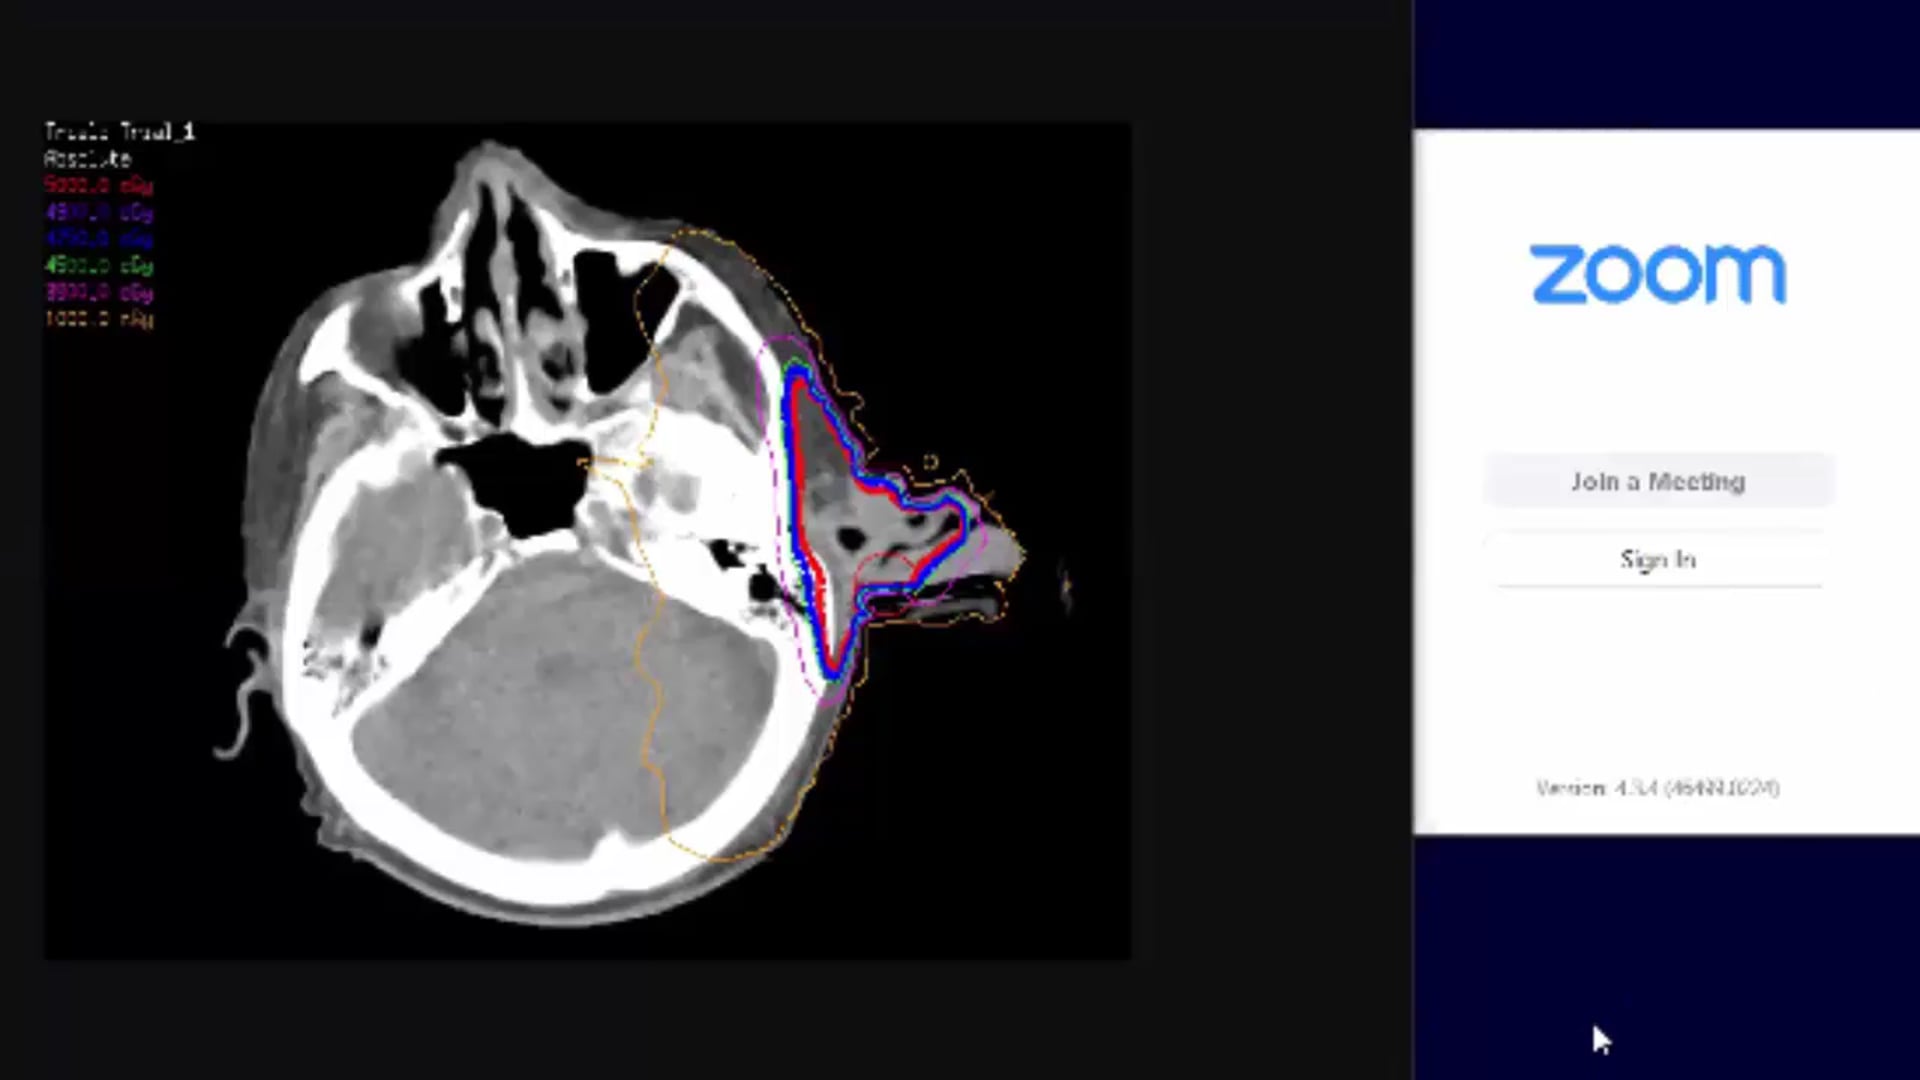

03/09/21- Dr. Kenneth Hu - Radiation Oncology - Head and Neck US

tongue-based cancer, dosimetry plan, treatment plan and contouring, contra-lateral node treatment, nasal pharynx treatment, bone invasive mass,